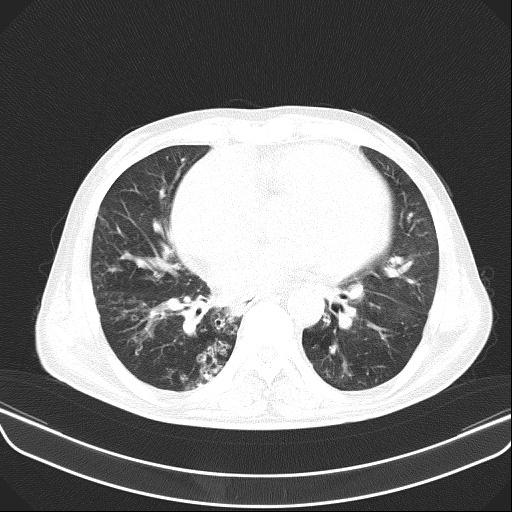

6月11日,会昌县人民医院呼吸内科接诊一呼吸衰竭的患者胡某,男性,54岁,主诉反复咳嗽、咳痰、气促10余年加重伴下肢浮肿10天入院。呼吸内科医生对胡某进行仔细查体:患者口唇及颜面、四肢紫绀明显,颈静脉怒张,桶状胸,肋间隙增宽,叩诊过清音,双肺呼吸音减弱,可闻及较多干湿性啰音,腹膨隆,肠鸣音减弱,双下肢重度浮肿。结合各类辅助检查,确诊胡某为“慢性阻塞性肺疾病、慢性呼吸衰竭、慢性肺源性心脏病失代偿期、重度肺动脉高压”。

不吸氧情况下胡某SPO2:67%,吸氧3L/min情况下SPO2:82%,治疗难度大,如何纠正严重的呼吸衰竭是重点。胡某重度浮肿、尿量少、腹胀明显、进食少,病情危重,随时有可能出现昏迷。同时,胡某神志清楚,无法配合无创双水平呼吸机辅助通气,不纠正呼吸衰竭,抗感染、祛痰、平喘、强心、利尿、扩血管等常规治疗几乎无效。

按照常规,医生会建议患者转ICU气管插管接有创呼吸机辅助通气或者转上级医院救治,但胡某拒绝转ICU,拒绝转上级医院,不接受气管插管及面罩式无创呼吸机辅助通气。经科内医生组讨论后决定:为避免患者气管插管或切开,使用经鼻高流量氧疗治疗,同时配合抗感染,雾化解痉祛痰,甲泼尼龙、多索茶碱平喘,托拉塞米、螺内酯利尿等治疗。经过13天时间治疗,胡某症状缓解、浮肿消退,好转出院。